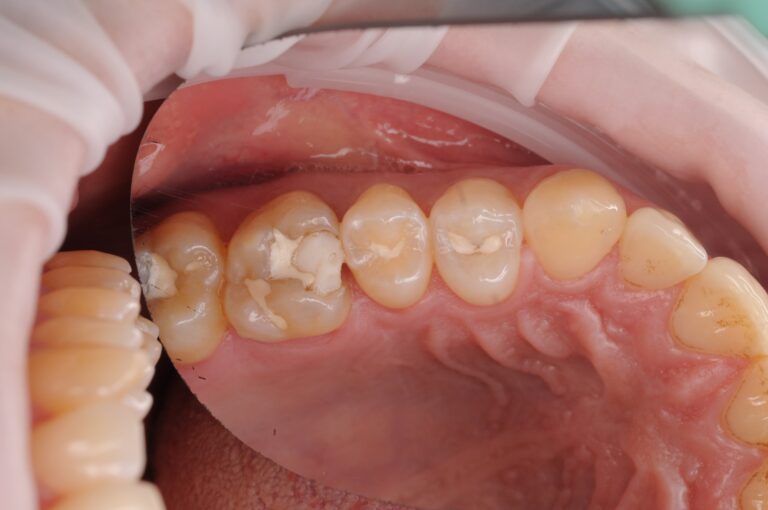

Первый снимок: старая большая пломба, под которой уже развился кариес.